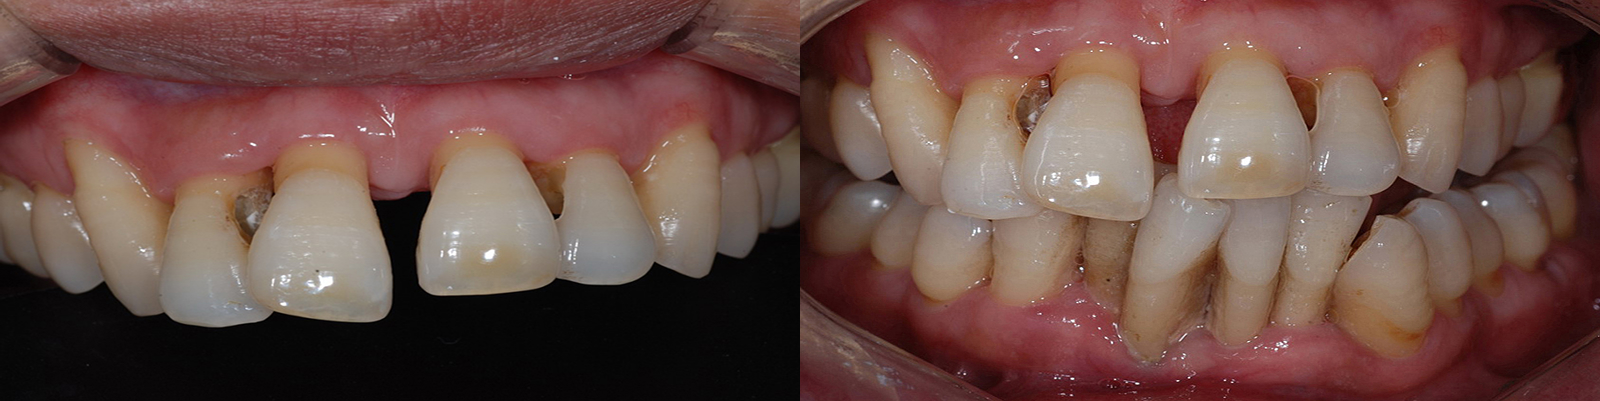

CASE.01

심한마모 치아 살리기